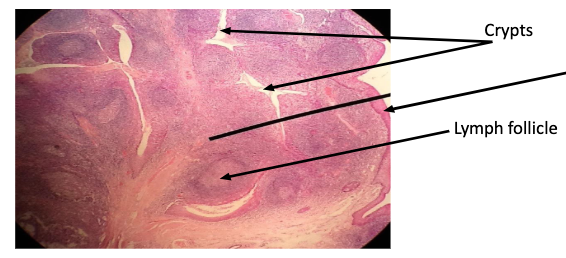

Peyer's patches

intestinal lymph node